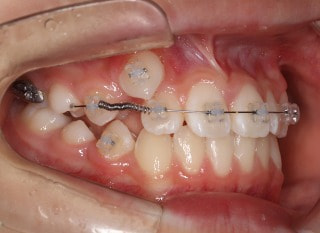

前歯装置装着時

小児期第一段階

終了時